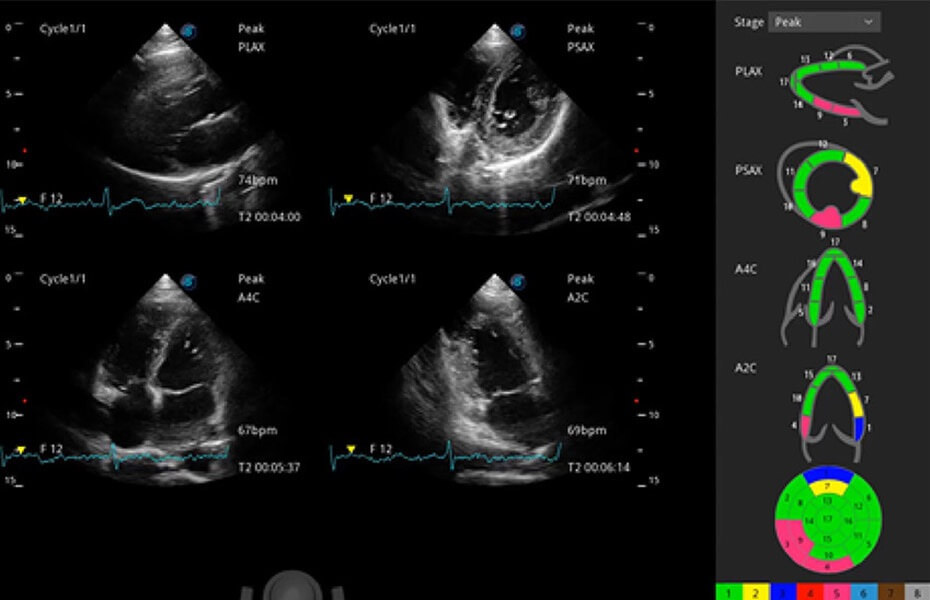

ProPet 60 作为一款高端台式动物超声设备,为动物医生的日常诊断提供了一系列贴合动物临床需求、解决临床实际问题的高级成像功能。凭借全系列高清探头,满足医生对腹部、心脏、生殖、浅表、肌骨等成像的所有需求,切实帮助您提升检查效率,提高诊断信心。